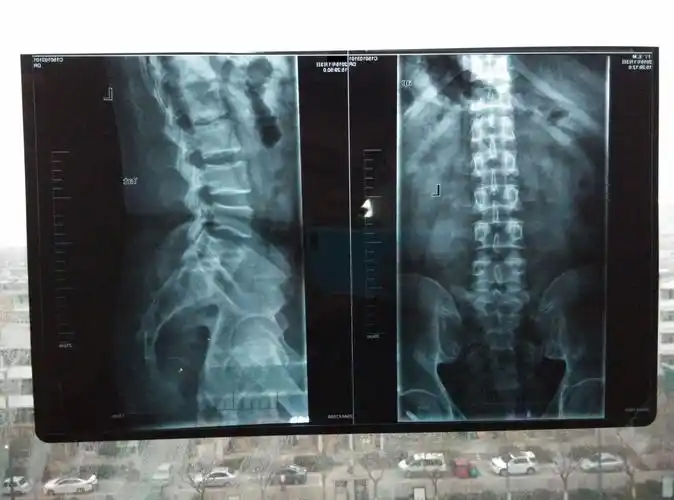

阜阳市中医医院骨科腰椎间盘巨大突出小切口开窗减压一例

术前x光片